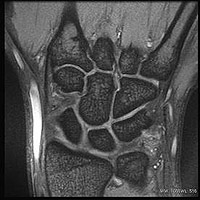

手根骨